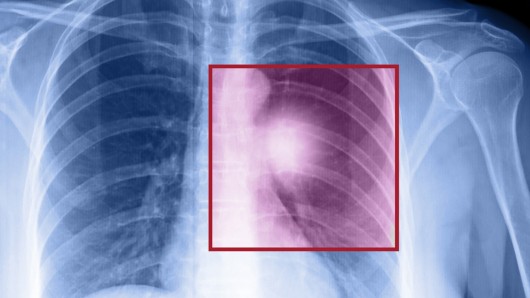

The Future is Here: Cancer Drug Developed by AI

The development of cancer drugs is a costly, expensive, time-consuming process that has a high probability rate of failure. On average, it takes 24 to 48 months to find a suitable candidate and costs upwards of $100 million. And in the end, roughly 95% of all potential drugs fail in clinical trials. Because of this, scientists are understandably looking for a way to speed up the discovery process.

That’s where the anti-cancer drug known as BPM 31510 comes in play. Unlike most pharmaceuticals, it was developed by artificial intelligence instead of a group of researchers toiling away in a lab. Created by biotech company Berg (named after real estate billionaire Carl Berg) the company seeks to use artificial intelligence to design cancer drugs that are cheaper, have fewer side effects, and can be developed in half the time it normally takes.

Towards this end, they are looking to data-driven methods of drug discovery. Instead of generating cancer drugs based on chemical compounds identified in labs, the company compares tissue, urine, and blood samples from cancer patients and healthy patients, generating tens of trillions of data points that are fed into an artificial intelligence system. That system crunches all the data, looking for problems.

BPM 31510, which is the first of Berg’s drugs to get a real-world test, focuses on mitochondria – a framework within cells that’s responsible for programmed cell death. Normally, mitochondria triggers damaged cells to die. When cancer strikes, this process goes haywire, and the damaged cells spread. Berg’s drug, if successful, will be able to restore normal cell death processes by changing the metabolic environment within mitochondria.

Speaking on the subject of the drug, which is now in human-clinical trials, Berg president and co-founder Niven Narain said:

BPM 31510 works by switching the fuel that cancer likes to operate on. Cancer cells prefer to operate in a less energy-efficient manner. Cancers with a high metabolic function, like triple negative breast cancer

, glioblastoma, and colon cancer–that’s the sweet spot for this technology.

All of these efforts are still in early days, and even on its accelerated timeline, BPM 31510 is still years away from winning an FDA approval. But, as Narain points out, the current drug discovery system desperately needs rethinking. With a success rate of 1 out of 20, their is definitely room for improvement. And a process that seeks to address cancer in a way that is more targeted, and more personalized is certainly in keeping with the most modern approaches to medicine.